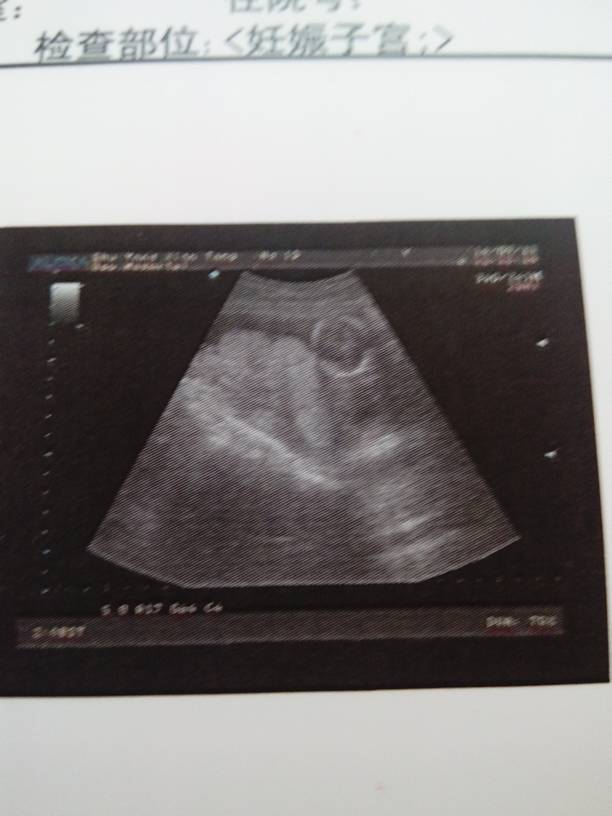

我15周+4天宫内见一胎儿,双顶径3.0cm,后壁胎盘,胎心博动143次/分,羊水深3.6cm,单 我15周+4天宫内见一胎儿,双顶径3.0cm,后壁胎盘,胎心博动143次/分,羊水深3.6cm,单活胎请帮我看看一切正常嘛??? 点击展开 妈咪妈呀 2014-09-11 15:37 为您推荐: 其他回答 正常。。。 醉爱 2014-10-18 20:02 正常。。。 幸福“宝贝” 2014-10-17 22:29 祝宝妈好孕,宝贝健康! 三月 2014-10-17 21:54 我的胎心147是男宝还是女宝? 小年糕 2014-10-17 14:45 从现在开始要增加肉类食品。 ok天秤座10 2014-10-08 07:52 加载更多 相关问题 怀孕第137天 胎儿双顶经4 6cm,股骨长3 0cm,心律143次/分,胎盘位于子宫前壁羊水深4 3cm 正常吗? 怀孕28周、胎盘厚3 6cm\钙化III级I度、羊水量正常、预产期是10月19号、能等到足月生吗? 怀孕29周+1 胎儿发育情况头位,胎头双顶径7 2cm\胎心144次/分、律齐、胎盘位于子宫前壁厚3 6cm\羊水深5